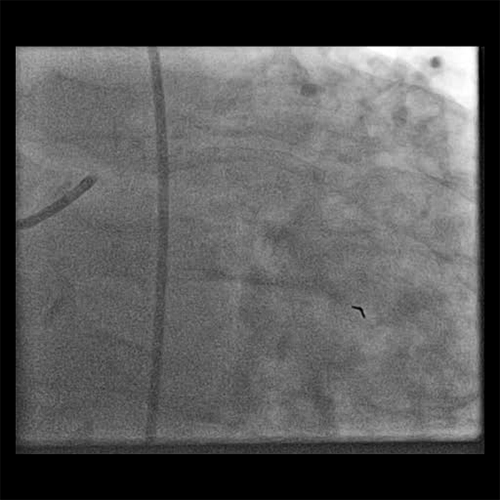

• Post wiring, the thrombus grade was 3 (Cine 2: Post Wire)